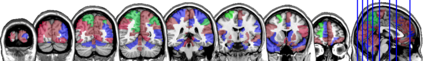

In this paper, we propose methods for functional predictor selection and the estimation of smooth functional coefficients simultaneously in a scalar-on-function regression problem under high-dimensional multivariate functional data setting. In particular, we develop two methods for functional group-sparse regression under a generic Hilbert space of infinite dimension. We show the convergence of algorithms and the consistency of the estimation and the selection (oracle property) under infinite-dimensional Hilbert spaces. Simulation studies show the effectiveness of the methods in both the selection and the estimation of functional coefficients. The applications to the functional magnetic resonance imaging (fMRI) reveal the regions of the human brain related to ADHD and IQ.